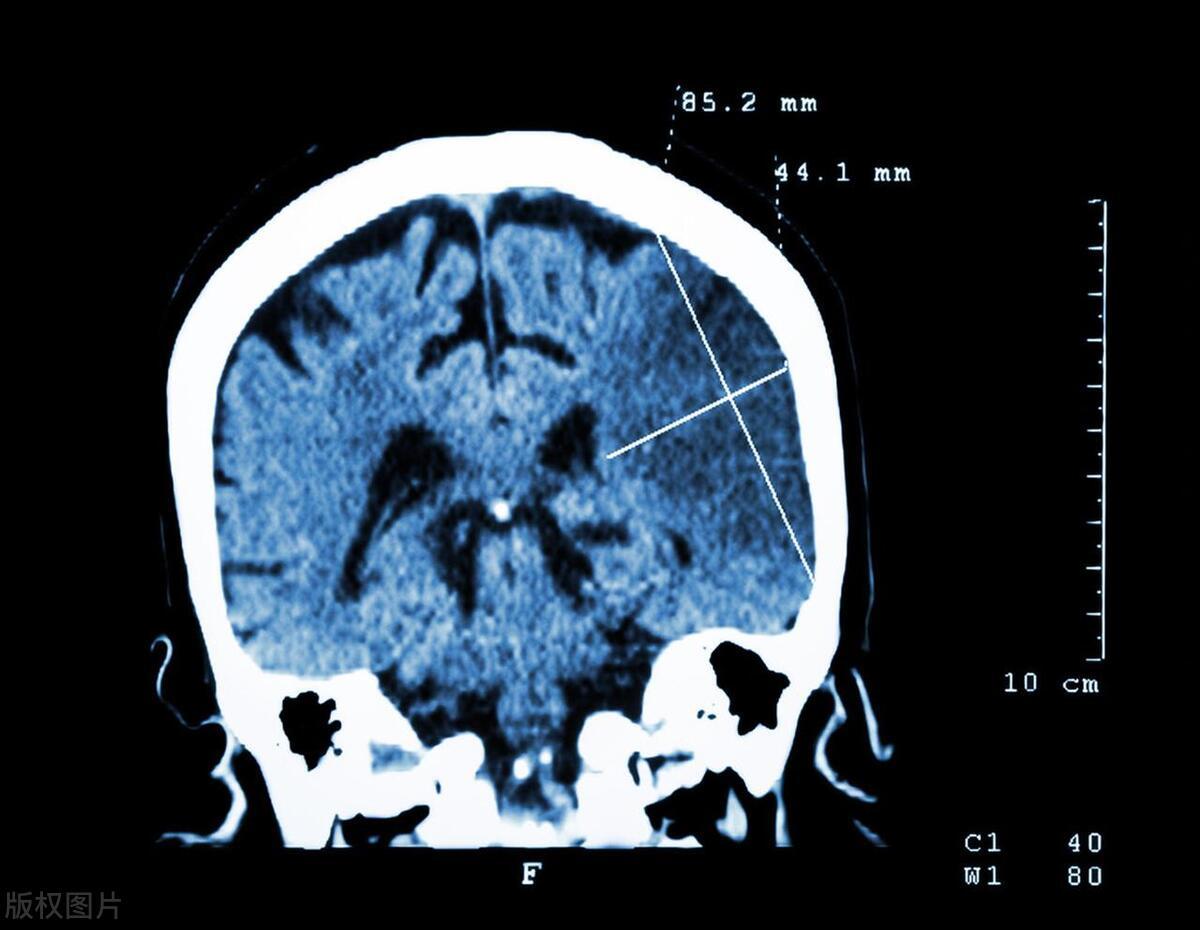

2. 腦卒中

腦卒中也稱爲"中風",是由於腦血管突然破裂或阻塞導致的腦組織損傷。腦卒中的症狀包括突然的肢體麻木、嘴歪眼斜、說話不利索、視力模糊、頭暈等。

然而,很多人會把這些症狀誤認爲是疲勞、偏頭痛或者是上了年紀的正常表現,從而延誤了治療的最佳時機。事實上,腦卒中發作後的4.5小時內是溶栓治療的黃金時間窗。如果錯過這個時間窗,即使搶救成功,患者也可能會留下後遺症。